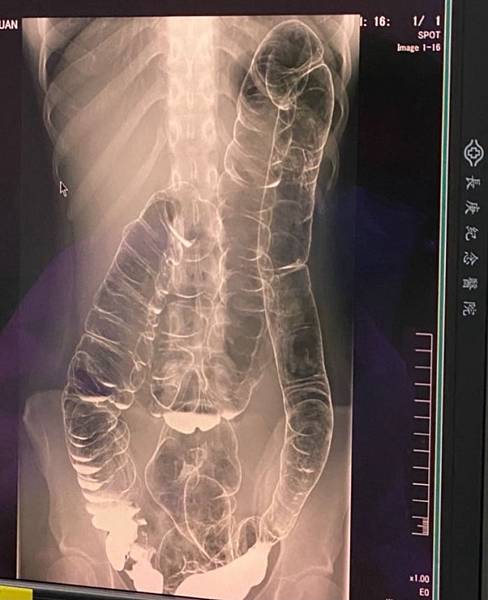

CXR才是診斷的經典:

右側橫膈下方有經典的Free air,

是胃/十二指腸或小腸或大腸破了!一個胃或腸的小破洞,電腦斷層無法判定哪兒破了,一般外科開下去發現是遠端降結腸(Distal descending colon)破了一個洞(0.5 cm),於是找直腸外科繼續完成手術。